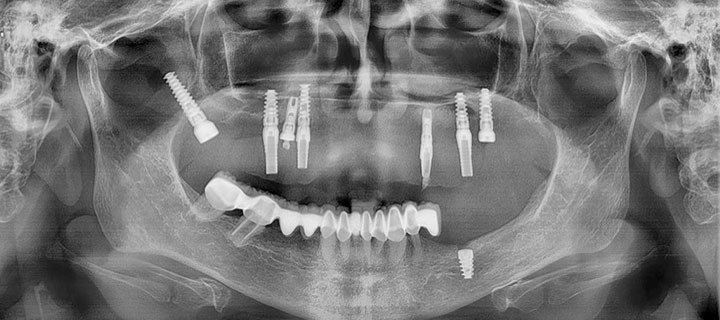

Paciente femenino de 68 años de edad, a la evaluación clínica, se observa edéntulismo total de la arcada superior, entre los hallazgos radiográficos, se encontraron dos implantes dentales a nivel de primeros premolares, así mismo, se observó poco remanente oseo en maxilar, se propuso la colocación de implantes dentales con la técnica all on 6 y un implante pterigoideo para refuerzo.

Rx panorámica postoperatorio inmediato de la colocación del implante pterigoideo

A los meses de espera de la osteointegración de los implantes, se procedió a la rehabilitación total de la cavidad oral, logrando devolverle a la paciente estabilidad, estética y función.